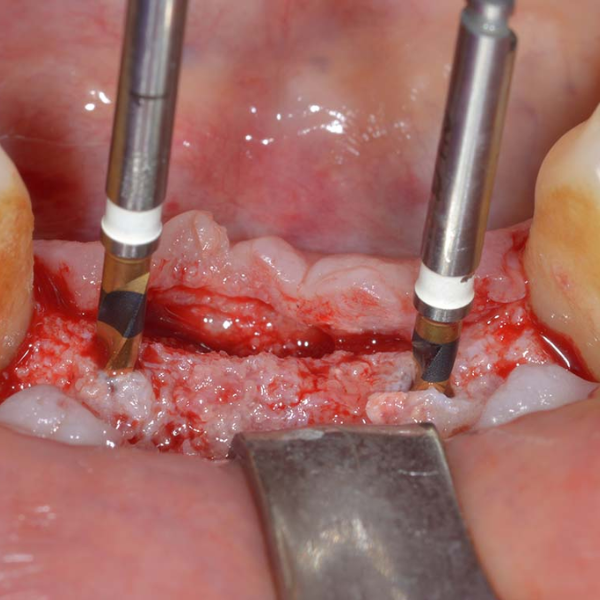

Patient suffered from localised periodontitis affecting all lower incisors with severe bone loss.